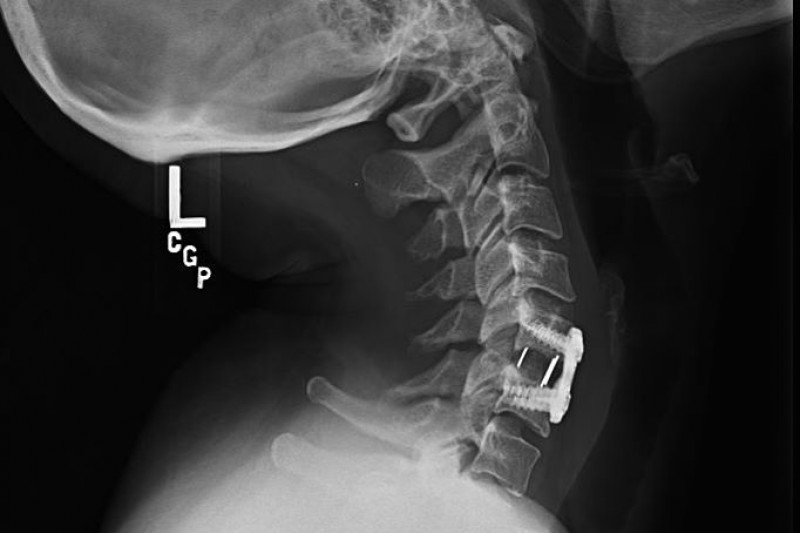

On March 10, 2016 I had a spinal fusion surgery (C5-6 ACDF) to remove a disc that was crushing my spinal cord. My surgery did not go well, and ever since then I've struggled with continuing neurological problems, unrelenting neck pain and spasms, and migraines that are triggered by my spine injury. I have three other herniated discs and nerve compression that covers the majority of my cervical spine and upper thoracic spine.

The fusion has caused the vertebrae above and below it to shift unnaturally, which disrupts the biomechanics in my spine. After going through countless invasive spine injections and other quasi-surgical procedures to reduce these problems, I'm still struggling with debilitating pain and never-ending headaches. I've literally had a migraine every single day since my surgery. Many of my medications are not covered by insurance, and in addition to continuing spine injections and physical therapy, I will also likely require another two surgeries to address the host of problems in my spine.

There were two surgery options: one is called an ACDF (anterior cervical discectomy and fusion), and the other is an ADR (artificial disc replacement). Both involve cutting through the front of my throat to get to my spine, removing the damaged discs, and taking the pressure off my spinal cord. (Trigger warning: actual post-op photo of my neck incision below).

The ADR was a better solution for me, but due to insurance issues, I ended up stuck with the inferior ACDF option. Click here for an animated video of the surgery. Now I will forever have a plate and giant metal screws in my spine. Over time, this will continue degrading the surrounding discs and vertebrae.

The fusion has caused the vertebrae above and below it to shift unnaturally, which disrupts the biomechanics in my spine. After going through countless invasive spine injections and other quasi-surgical procedures to reduce these problems, I'm still struggling with debilitating pain and never-ending headaches. I've literally had a migraine every single day since my surgery. Many of my medications are not covered by insurance, and in addition to continuing spine injections and physical therapy, I will also likely require another two surgeries to address the host of problems in my spine.

The ADR was a better solution for me, but due to insurance issues, I ended up stuck with the inferior ACDF option. Click here for an animated video of the surgery. Now I will forever have a plate and giant metal screws in my spine. Over time, this will continue degrading the surrounding discs and vertebrae.